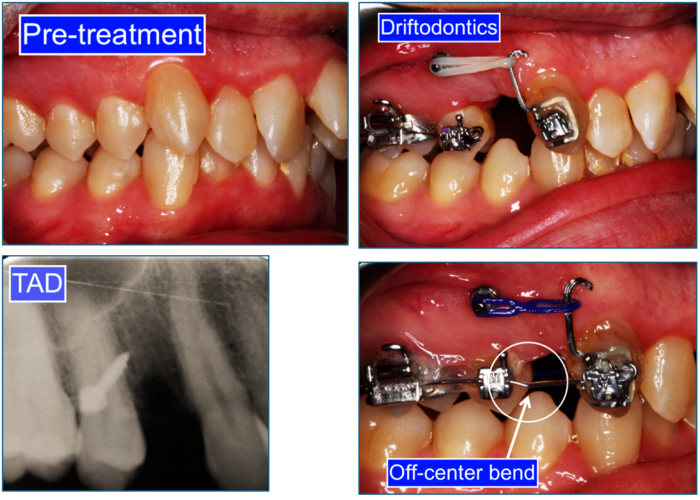

The author is presenting a 36-year-old Caucasian male, with a true maxillary dentoalveolar protrusion and severe crowding.  The mandible is within the norm. The chief complaint was, “my upper front teeth are too far forward, too crowded and I cannot keep my lips together.”

The treatment comprised of odontectomy of maxillary first bicuspids, TADs and Straight wire appliance.  The sequence was as follows:

1. Odontectomy of #14(5) & #24(12)

2. Placement of TADs

3. Bonding the power arms on #13(6) & #23(11)

4. Driftodontics – retraction with Elastomeric chains without a wire

5. Placement of the Off-center bend on the sectional a .016 SS wire